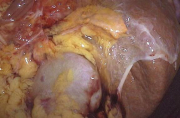

| 15:18, 4 בנובמבר 2012 | אדרנל1014.png (קובץ) |  |

132 קילו־בייטים | Motyk | 1 | |